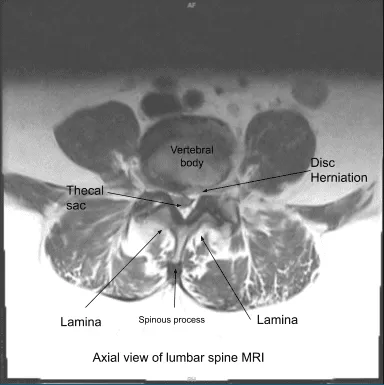

We discussed systemic complications including blood clot, cardiac, pulmonary, and neurological complications including blindness and death. The patient understood and signed an informed consent. MRI findings supported the diagnosis of spinal canal stenosis and neural foraminal narrowing.

Axial view of Lumbar Spine MRI